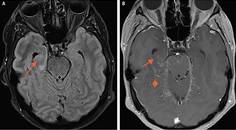

Case Report: Seizure, Fever, Hallucinations, & Vision Loss

Elizabeth Carroll, MD; Brian J. Williams, MDElizabeth Carroll, MD; Brian J. Williams, MD - Epilepsy & Seizures